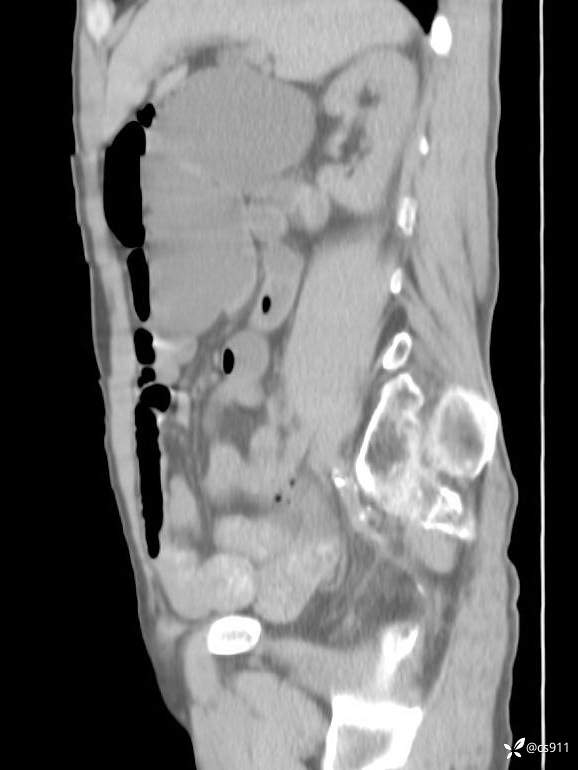

急腹症之急诊CT,原因?答案公布

男,77岁,腹痛、腹胀伴恶心呕吐1天。呕吐胃内容物,非喷射性呕吐,有咖啡色样胃内容物,诉有胃穿孔病史。查体:全腹平,下腹部压痛,全腹无反跳痛,叩诊呈浊音,移动性浊音阴性,肠鸣音减弱,1-2次/分。肛检:直肠未扪及明显肿物,可触及大量粪块。

T 36.6℃ P 80次/分 R 26次/分 BP 100/60mmHg

白细胞(WBC) H 14.55 10e9/L 4-10

红细胞(RBC) 4.58 10e12/L 4.3-5.8

中性粒细胞百分率(NEUT%) H 85.7 % 40-75

血淀粉酶(AMY) HH 1859 U/L 35-135

癌胚抗原(CEA) H 27.44 ng/ml 0-5

呕吐物 潜血试验 * 阳性 阴性

患者轮椅入室检查神志清楚, 能配合摆位和呼吸